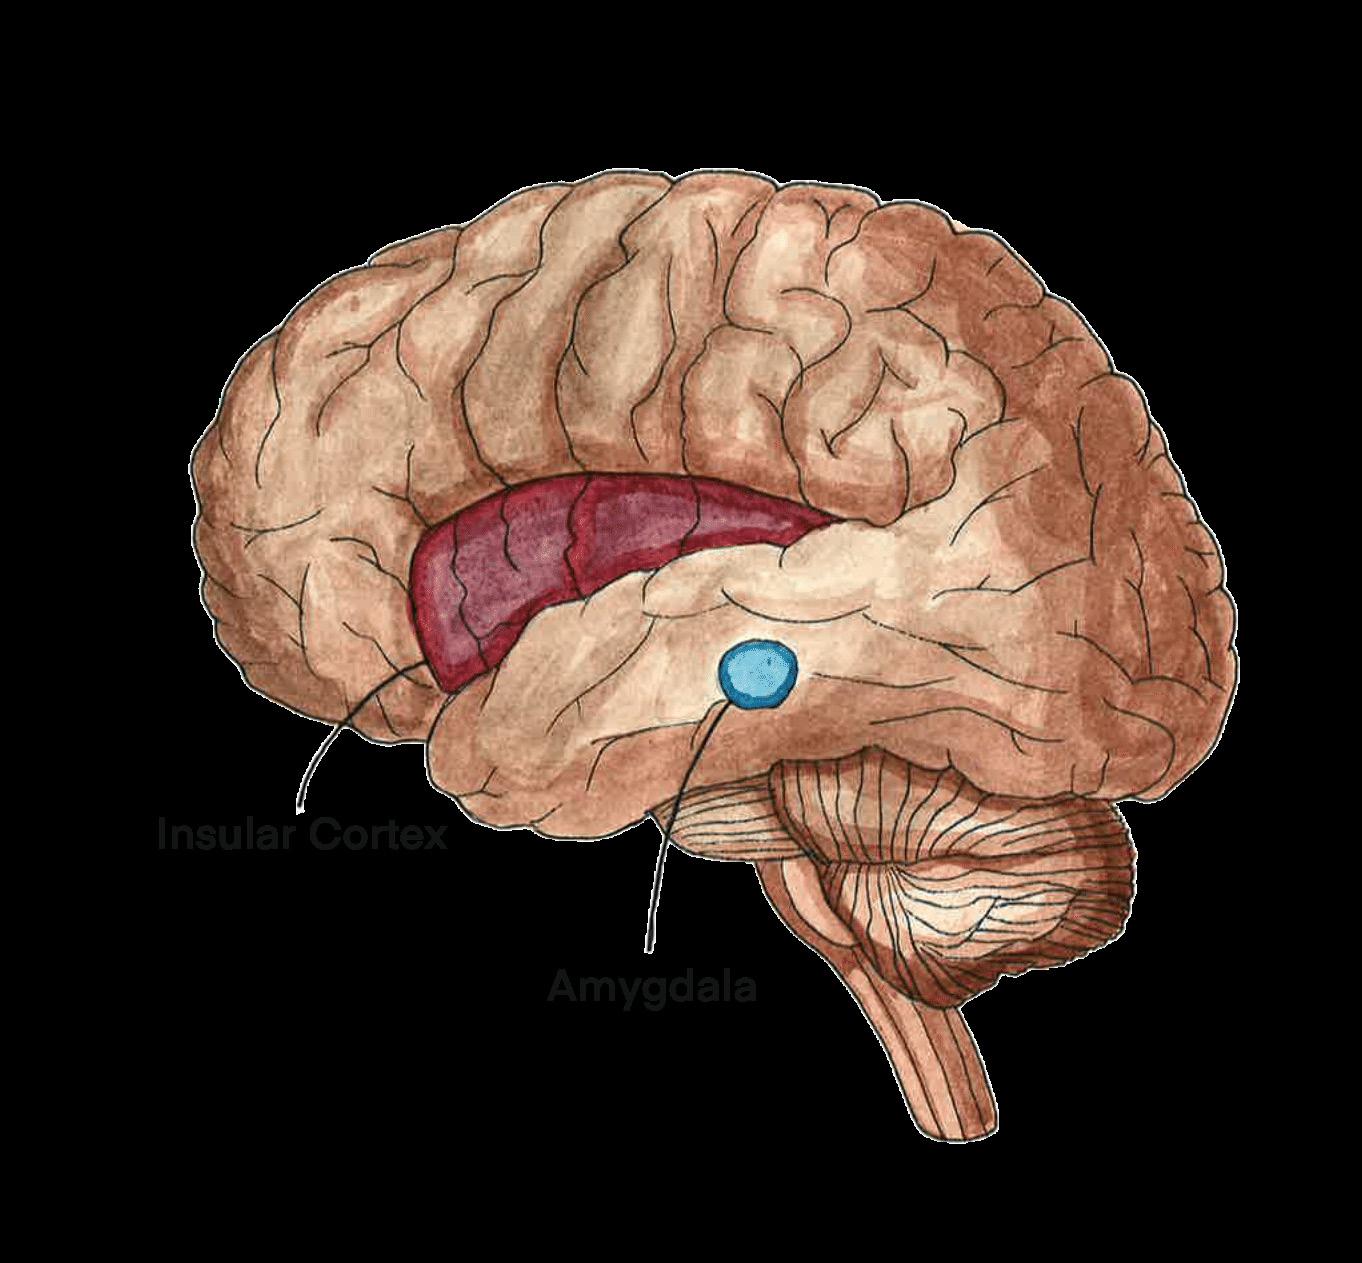

Abnormalities in the brain are being investigated in an attempt to uncover the cause of FSDs, with the existing research focusing primarily on functional neurological disorder [44, 45, 46]. Neuroimaging has uncovered differences in brain structure and function in individuals with FND compared to individuals without FND [28]. Individuals who reported severe impairment in daily functioning due to FND displayed reduced volume of their insular cortex, a brain region that influences one’s sense of self-awareness, emotional processing, and interoception [28, 47]. Interoception refers to the awareness of the internal bodily signals, such as the sensation of pain [48]. When

interoception is altered, individuals may experience increased pain, leading to more intense symptoms [28, 49, 50]. Functional imaging is an additional tool in the characterization of FND, as it can provide evidence of activity changes in specific areas of the brain [28]. In individuals with FND, there can be decreased activity in areas associated with movement, such as the supplementary motor area (SMA), and increased activity in areas in the insular cortex [28, 51]. Additionally, those with FND have increased neuronal activity between parts of the limbic system, a part of the brain that regulates emotions, and the motor circuit [28]. The increased activity potentially indicates that there is heightened limbic influence over motor behavior [28]. Promoted limbic and insular activity may shed light on how psychological symptoms lead to the manifestation of seizures and other somatic symptoms in FND [28, 51, 52]. Although brain activity changes have only been concretely studied in FND, similar mechanisms may be at play in other FSDs, warranting further research [53].